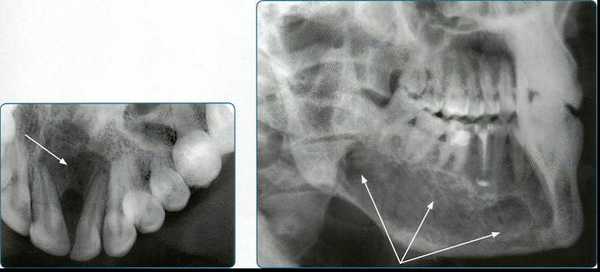

4. Панорамная томография

Более трех десятилетий назад в арсенал рентгенодиагностики заболеваний зубочелюстной системы, ЛОР-органов и других отделов черепа вошла панорамная рентгенография. При этом методе исследования аппликатор рентгеновской трубки вводят в рот пациента, а кассета располагается вокруг верхней или нижней челюстной дуги. В обоих случаях пациент придерживает кассету с наружной стороны ладонями, плотно прижимая ее к мягким тканям лица.

Проводится также и боковая панорамная томография, на боковом панорамном снимке одновременно отображаются зубы верхнего и нижнего ряда каждой половины челюсти.

Прямые панорамные рентгенограммы имеют преимущество перед внутриротовыми снимками по богатству деталями изображения костной ткани и твердых тканей зубов. При минимальной лучевой нагрузке они позволяют получить широкий обзор альвеолярного отростка и зубного ряда, облегчают работу рентгенолаборанта и резко сокращают время исследования. На этих снимках хорошо видны полости зуба, корневые каналы, периодонтальные щели, межальвеолярные гребни и костная структура не только альвеолярных отростков, но и тел челюстей. На панорамных рентгенограммах выявляются альвеолярная бухта и нижняя стенка верхнечелюстной пазухи, нижнечелюстной канал и основание нижнечелюстной кости.

На основании панорамных снимков диагностируют кариес и его осложнения, кисты разных типов, новообразования, повреждения челюстных костей и зубов, воспалительные и системные поражения. У детей хорошо определяется состояние и положение зачатков зубов.